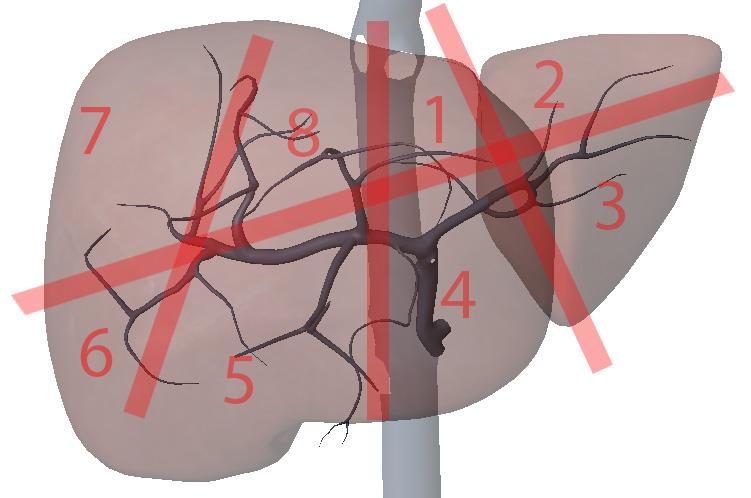

What is section 1?

Left Medial superior

What is section 2?

Left lateral superior

What is section 3?

Left lateral inferior

What is section 4?

Left medial inferior

What is section 5?

Right anterior inferior

What is section 6?

Right posterior inferior

What is section 7?

Right posterior superior

What is section 8?

Right anterior superior

What are the hepatic veins key to?

division of the liver longitudinally

What are the portal veins key to?

transverse division of the liver